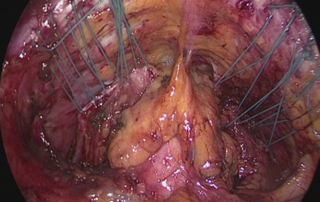

Hemorrhagic ascites and pleural effusion: an uncommon presentation of endometriosis

DOI: 10.36205/trocarvid1.2021001